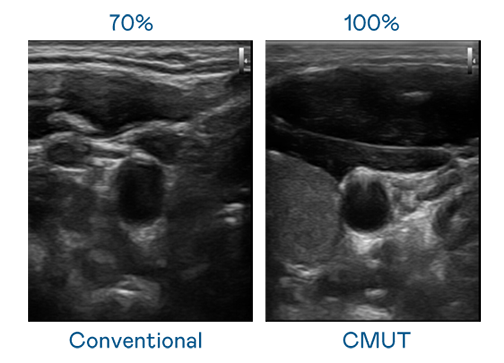

LEYU官網(wǎng)運(yùn)用 TFT 陣列 (Array) 制程延伸尖端感測(cè)技術(shù),開(kāi)發(fā)出多種感測(cè)元件的LEYU官網(wǎng)。高解析度、品質(zhì)穩(wěn)定且可量產(chǎn)的 CMUT 元件,可制作高解析度超音波探頭、貼片型探頭,對(duì)病患實(shí)施精準(zhǔn)檢測(cè)與長(zhǎng)時(shí)間生理監(jiān)測(cè)。